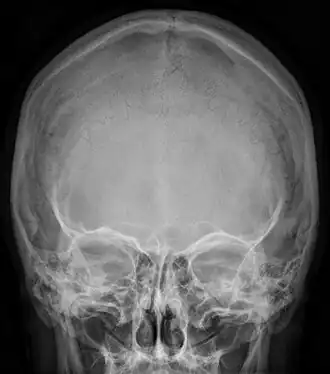

![]() Radiograph of the skull showing an interparietal bone between the occiput and parietal bones | |

In humans, it corresponds to the upper portion of the squama of the occipital bone that lies superior to the highest nuchal line and is completely fused to the supraoccipital. However, in some individuals this portion remains separate from the rest of the occipital bone throughout life. In such cases, this separate bone is particularly referred as Inca bone. Inca bones in humans were first found in the skulls of contemporary indigenous peoples of the southern Andes as well as in those of mummies of the Inca civilization. Although the Inca bone was originally encountered as a variation in South American and Latin American cranial remains, the variation occurs in people from all geographic regions of the world and is by no means indicative of South/Latin American origin.